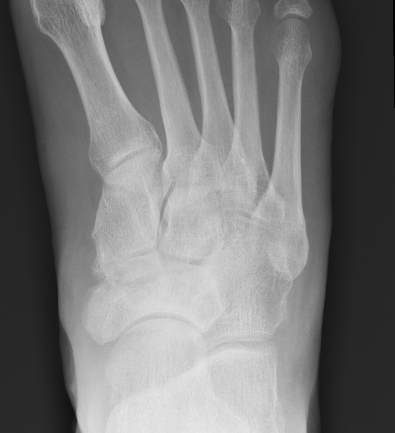

Xray

Sclerosis / Fragmentation

Talonavicular osteoarthritis

Talocuneiform osteoarthritis

Midfoot collapse